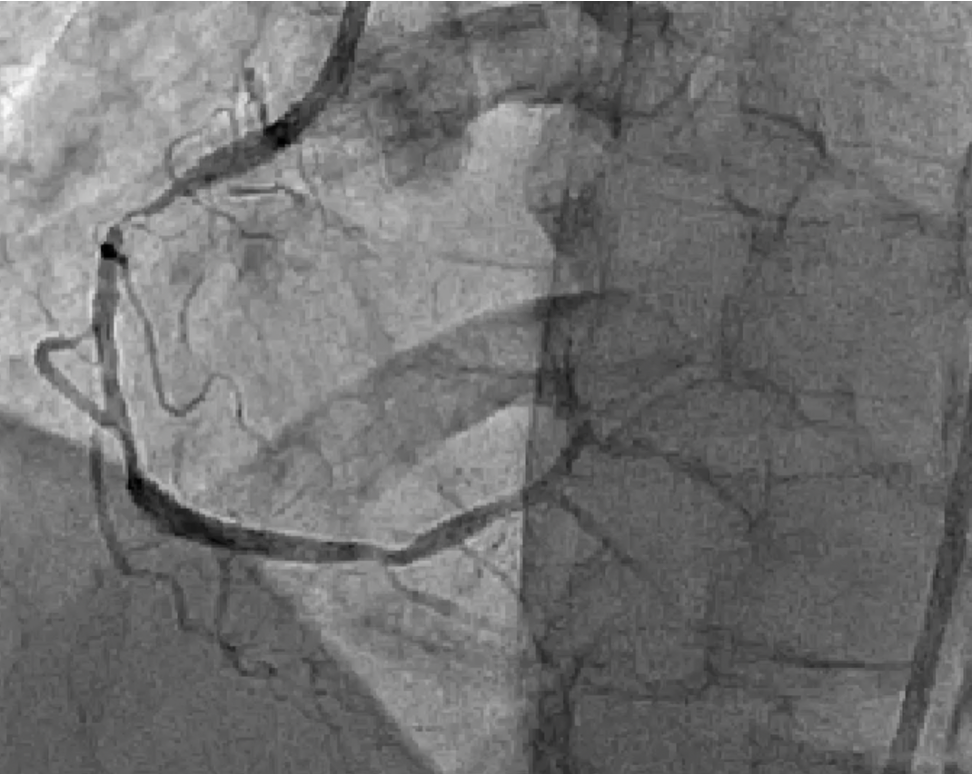

66 Yr Old male with Diabetes, HTN , Dyslipidaemia presented with Angina Class III diagnosed as NSTEMI with Acute Decompensated Heart Failure with Moderate LV systolic dysfunction. on the basis of History and investigations patient taken up for coronary angiogram which revealed triple vessel disease

Relevant Catheterization Findings

A temporary pacing lead was placed in view of triple vessel disease and potential for bradyarrhythmias during atherectomy.

A 6F JR guiding catheter was engaged at the RCA ostium. The lesion was initially crossed using a Sion Blue wire, which was parked distally into the posterior descending artery (PDA).A 0.75 mm CTO balloon was then advanced but failed to cross the heavily calcified lesion. The wire was subsequently exchanged for a RotaWire, and rotational atherectomy was performed in three sequential runs:

- Proximal to mid RCA

- Mid RCA

- Mid to early distal RCA

When even the smallest CTO balloon failed to cross, the burr became the breakthrough. Rotational atherectomy transformed an unyielding, calcified RCA into a successfully revascularized vessel. Guided by IVUS and supported by meticulous technique, the procedure achieved excellent stent expansion, optimal apposition, and restored TIMI III flow — reaffirming that in complex, calcified coronary lesions, Rota ablation remains the key when nothing else can pass